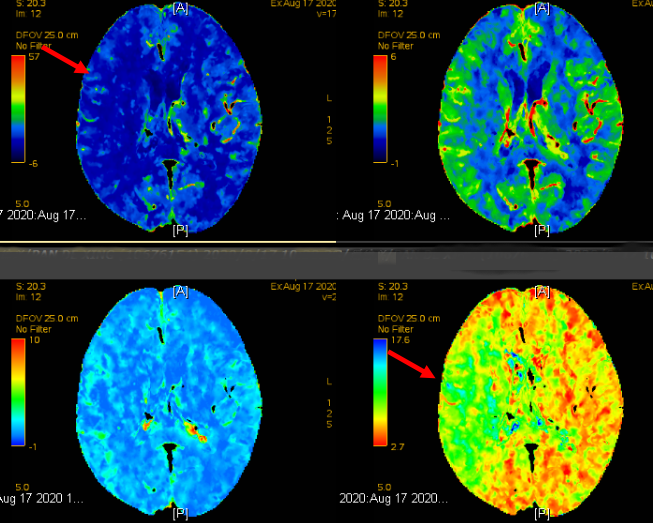

图中红色箭头部分为急性缺血性卒中早期,可挽救的脑卒中区域

家住天通苑67岁的刘先生被急救车送到北京清华长庚医院急诊神经内科后,绿色通道医师经神经系统查体及影像学检查,判断患者为急性缺血性脑卒中,左侧颈内动脉闭塞,影像发现患者左侧脑组织内有大片的可挽救的脑组织。“有些遗憾,如果能再早一步到达急诊,发病4.5小时内,我们就能用药溶栓打通那根阻塞的颈动脉,好在也还算及时,24小时内我们还有机会通过手术尝试再通血管。”神经内科急诊医师王也当机立断,联络麻醉科、导管室,启动绿色通道绝急手术。